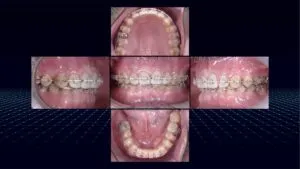

【症例のご紹介:前院で気になっていることを解決してもらえなかったと当院へのご来院】

今回ご紹介する患者さんは、元々、前歯の見た目を気にされており、その審美的な改善を希望して別の歯科医院にご相談されたという経緯をお持ちでした。ご自身の笑顔に自信を持ちたい、人前で口元を気にせず自然に笑いたいという切実な思いを抱えていらっしゃったのだと感じます。

しかし、残念ながら前院では、患者さんが最も気にされている前歯の問題に対して具体的な改善策が示されることなく、他の部分の治療が淡々と進められていったそうです。そしてご自身の悩みの核心に触れてもらえないまま時間だけが過ぎていく状況は、治療へのモチベーションを維持することも難しくなっていき、大きな不安と不信感につながったのだと思われます。

「必要な治療が沢山あるのかもしれないが、一番気になっていることが解決されないまま治療が進んでいき、最終的には自分が気になってることも解決されて自分のなりたい姿になれるのだろうか」

このような不安が募っていかれ、セカンドオピニオンを求めて当院の扉を叩いてくださいました。

▼実際の症例はこちらの投稿をご覧ください